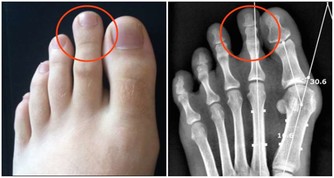

3、痔瘡也是因為缺乏維生素B2引起的。

輕微缺乏維生素B2人體不會有任何感覺,但到一定程度時就會出現明顯的癥狀,首先,在人體最薄弱的地方,通常是消化道的首尾兩端,即口腔或肛門的局部,出現充血、腫脹,隨後皮膚或粘膜出現潰瘍,然後開始出血,這即是口腔潰瘍和痔瘡。如果長期缺乏維生素B2,那麼人體其它部位也會出現同樣的癥狀。